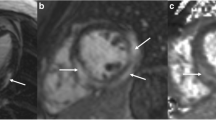

A male patient with non-consanguineous parents was healthy until the age of 4 years when he started to develop episodes of fever and chest discomfort. At the initial presentation, electrocardiography (ECG) showed sinus tachycardia with T-wave inversions and his C-reactive protein (CRP) was elevated (57 mg/L). He was concluded to suffer from mild myocarditis from which he recovered well. At the age of 5 years, he experienced another episode of chest pain and sinus tachycardia with T-wave inversions. CRP (58 mg/L) and troponin I (TnI) (2.1 ng/mL; normal < 0.03 ng/mL) were elevated. Following these first episodes, his growth, physical abilities, and developmental path continued to progress despite the recurrent myocarditis episodes. He received a diagnosis of allergic asthma and underwent treatment for it at the age of 9. He continued to suffer recurrent febrile episodes accompanied by chest pain, tachycardia, an elevated troponin T (TnT) and T-wave inversions in his ECG. Representative ECG findings consistent with myocarditis episode (TnT 485 ng/L, normal < 50 mg/L) at the age of 17 years are shown in Fig. 1A. During that episode, echocardiography showed a mild and transient reduction in left ventricular function. Myocardial magnetic resonance imaging (MRI) (Fig. 1B) demonstrated edema and enhancement consistent with myocarditis. Cardiac muscle antibodies were negative, and no evidence of respiratory infection pathogens was found (Supplemental Methods). The patient did not develop clinical or laboratory findings suggestive of HLH [18] Histological staining of myocardial biopsies collected from four locations were positive for CD3+ T cells (14/mm2) and macrophages consistent with myocarditis [9]. The myocardial biopsy was negative for TIM-3 expression (Fig. 1C). Beginning at the age of 17 years, febrile myocarditis episodes were treated with anakinra, an IL-1β receptor antagonist (Kineret®, 100 mg daily, 4 to 7 days), with a good clinical response. Due to successful anakinra response, the patient has not required hospitalization. Despite the tonsillectomy due to episodes of tonsillitis, he has not encountered additional health concerns.

(A) Representative electrocardiographs (ECG, 50 mm/s) on days 1 to 5 of hospitalization during an episode of acute myocarditis at age 17 years (B) Late gadolinium enhancement pattern (arrows) consistent with myocarditis in cardiac MRI (C) Representative images of TIM-3 immunostaining in myocardium biopsies. TIM-3 staining was positive (red arrows) in the control and negative in the patient’s samples